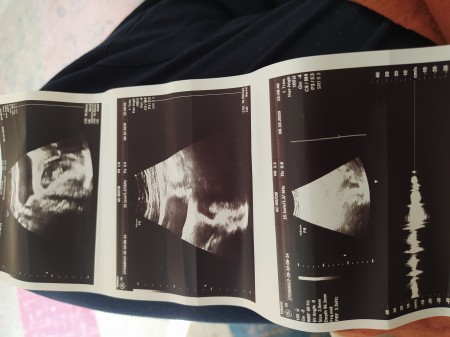

Geç döllenme olabilir cnm benim 4000 küsürdu kese göründü bebek gmrünmedi şimdi 8 haftalık kalp atışında duydum bak benim kesenin görüntüsünü atım sana

image

Ya çok benziyor aslında içim rahatladı

(115 puan)

Evet benziyor cnm geç döllenme olabilir o yüzden bekle biraz 7 haftalıkken de kalp atışını duydum bebeğide gördüm

Bak buda bebek gözüktüğü ultrason